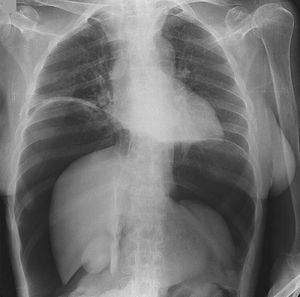

Pneumoperitoneum (gas within the peritoneal cavity, and is often the harbinger of a critical illness.).The most common cause of pneumoperitoneum is from the disruption of the wall of a hollow viscus

The diaphragm is the white line that the heart is sitting on halfway from both margins of the body. Definitely no hernia there :) but it is pushed upwards because of the increased intra-abdominal pressure.

Major causes include traumatic intubation, traumatic CPR , perforation during endoscopy, vigorous abdominal CPR, since its a "massive" pneumoperitoneum. Minor causes include GI perforation due to ulcers, tumors,foreign body,etc.